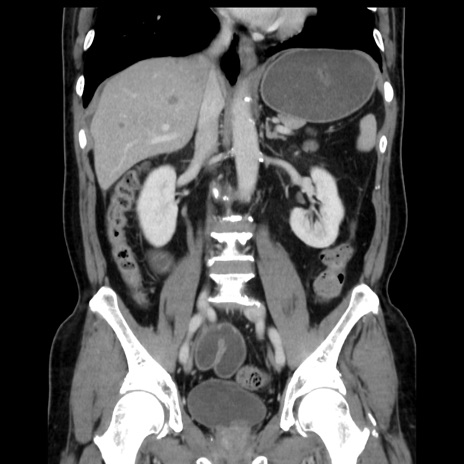

症例16(冠状断像)

【症例】 70歳代男性

【主訴】 腹痛、嘔吐

【現病歴】 約1ヶ月前より間欠的に腹痛と嘔吐あり、当院消化器内科を受診したところCTで多発する肝臓のLDAを指摘され、精査中であった。以降は消化器症状は安定していたが、2日前より嘔気と腹痛があり、同日より排便・排ガスが消失した。改善認めず、 本日、救急外来を受診した。

【既往歴】 大腸ポリープ切除後。

【身体所見】意識清明・会話良好、BT 36.3℃、BP 127/80mmHg、 P 80bpm、腹部:膨満あり、平坦・軟、上腹部正中および下腹部正中に圧痛あり、反跳痛なし、筋性防御なし。

【データ】WBC 7200、CRP 0.77